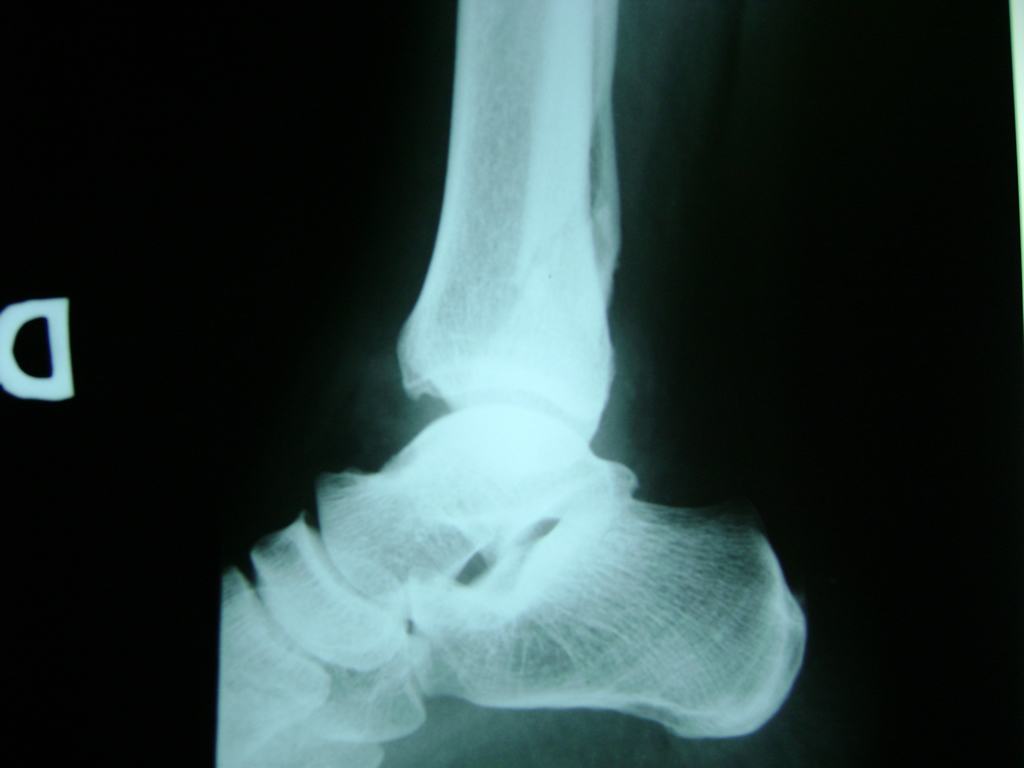

Una fractura de tobillo es la rotura de uno o más de los huesos del tobillo. Estas fracturas pueden ser:

- Parciales (el hueso está sólo parcialmente fisurado, no del todo).

- Completas (el hueso está perforado y está en 2 partes).

- Producirse en uno o ambos lados del tobillo.

Algunas fracturas de tobillo pueden requerir cirugía si:

- Los extremos de los huesos están desalineados entre sí (desplazados).

- La fractura se extiende hasta la articulación del tobillo (fractura intra-articular).

- Los tendones o ligamentos (tejidos que sujetan los músculos y los huesos entre sí) están rotos.

- El médico cree que sus huesos probablemente no sanen apropiadamente sin cirugía.

- El médico considera que la cirugía puede permitirle una recuperación más rápida y confiable.

- En los niños, la fractura involucra la parte del hueso del tobillo donde el hueso está creciendo.